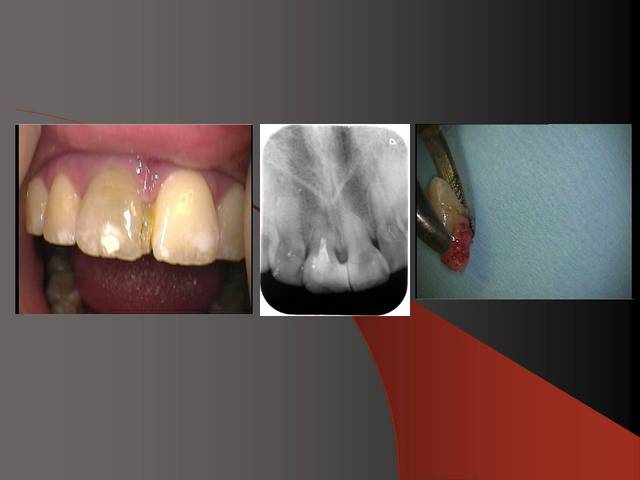

J´ai mis des photos pour mieux voir....

Merci pour ta remarque.C´est vrai que cela est mieux si on ne prérare pas ou presque pas les prep cap à cause des shippings . Normalement je ne les prépare pas, je choisis une forme (avec angle et longueur diiférents) selon le cas et ensuite je les cémente.

Sur la photo 5 on voit que je prépare surtout le titane de l´implant, le titane ne donne pas beaucoup du chaud quand il est préparé avec l´eau (pas comme aluminium par exemple).

Photo 2 du dernier cas, je crains beaucoup pour la plaque d'os en vestibulaire, même en flapless.